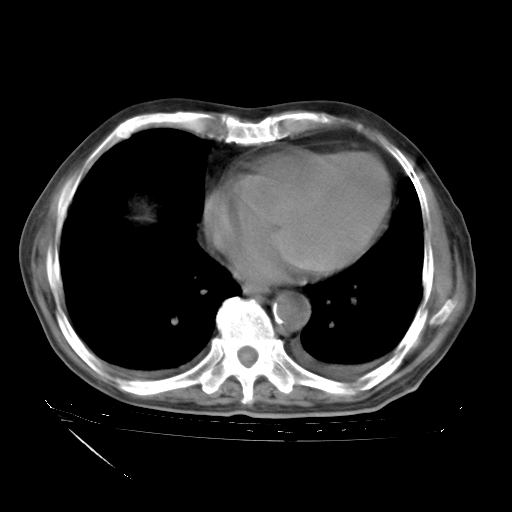

补充下:5月9日胸部CT:似乎已见双下肺胸腔积液了,鉴于目前有下肢水肿,肝功示:白蛋白低,应注意多浆膜腔积液(漏出液可能大?),需注意!

甲强龙80mg/日+抗结核治疗(异烟肼+利福霉素+乙胺丁醇)10天。复查肺部CT。

治疗10天肺部CT